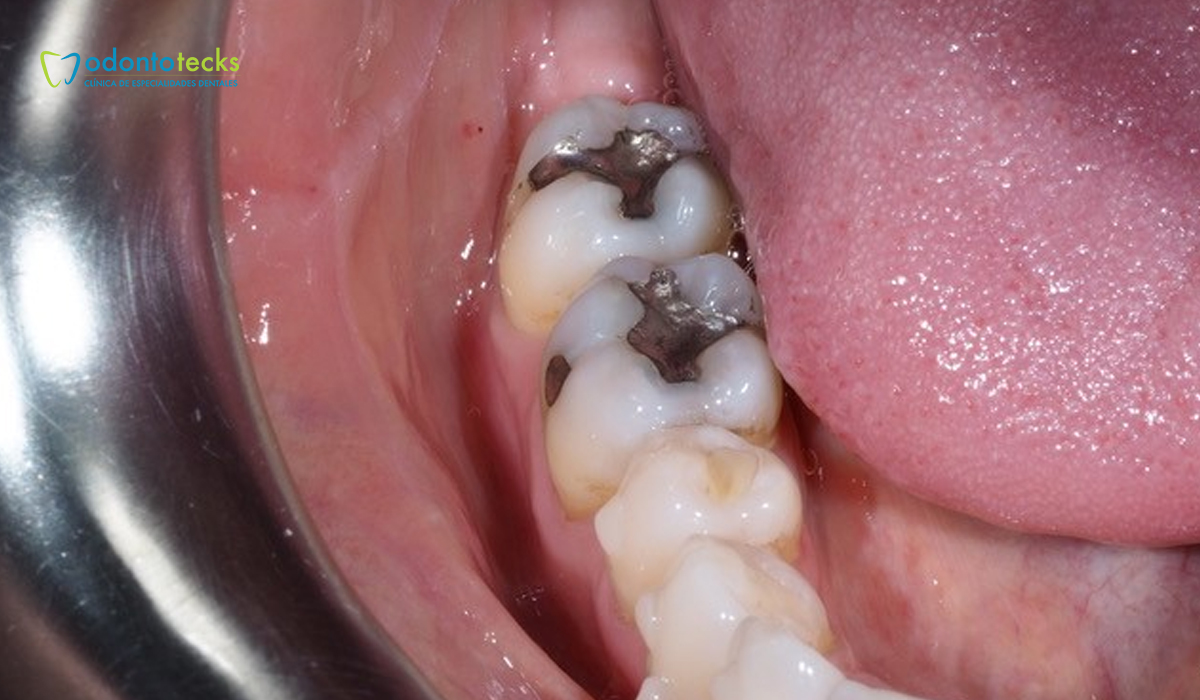

Las amalgamas son restauraciones dentales que reparan la pieza dental dañada por caries. Estas logran devolver la funcionalidad y la forma natural a la pieza. El especialista comienza por retirar todo el material infectado por la caries para posteriormente limpiarlo de manera profunda, luego de este proceso procede a realizar la obturación con el empaste de restauración indicado. Entre los principales materiales con los que la amalgama es realizada se encuentran metales como la plata, el mercurio, el estaño y el cobre.

El objetivo de rellenar los espacios es cerrar el paso para que las bacterias sigan desarrollándose y prevenir futuras caries. Entre las principales ventajas que la amalgama tiene están:

Gracias a su durabilidad, este tipo de empaste es usualmente la mejor opción para las caries que se desarrollan en las piezas posteriores las cuales requieren de mayor fuerza masticatoria. La amalgama se endurece en menor tiempo que otros empastes por los cual es ideal para colocarse en zonas que son difíciles de mantener secas durante la colocación, como por ejemplo en la línea de las encías. Este tipo de tratamiento suele ser indicado en pequeños ya que el tiempo para colocarla es inferior a otros.